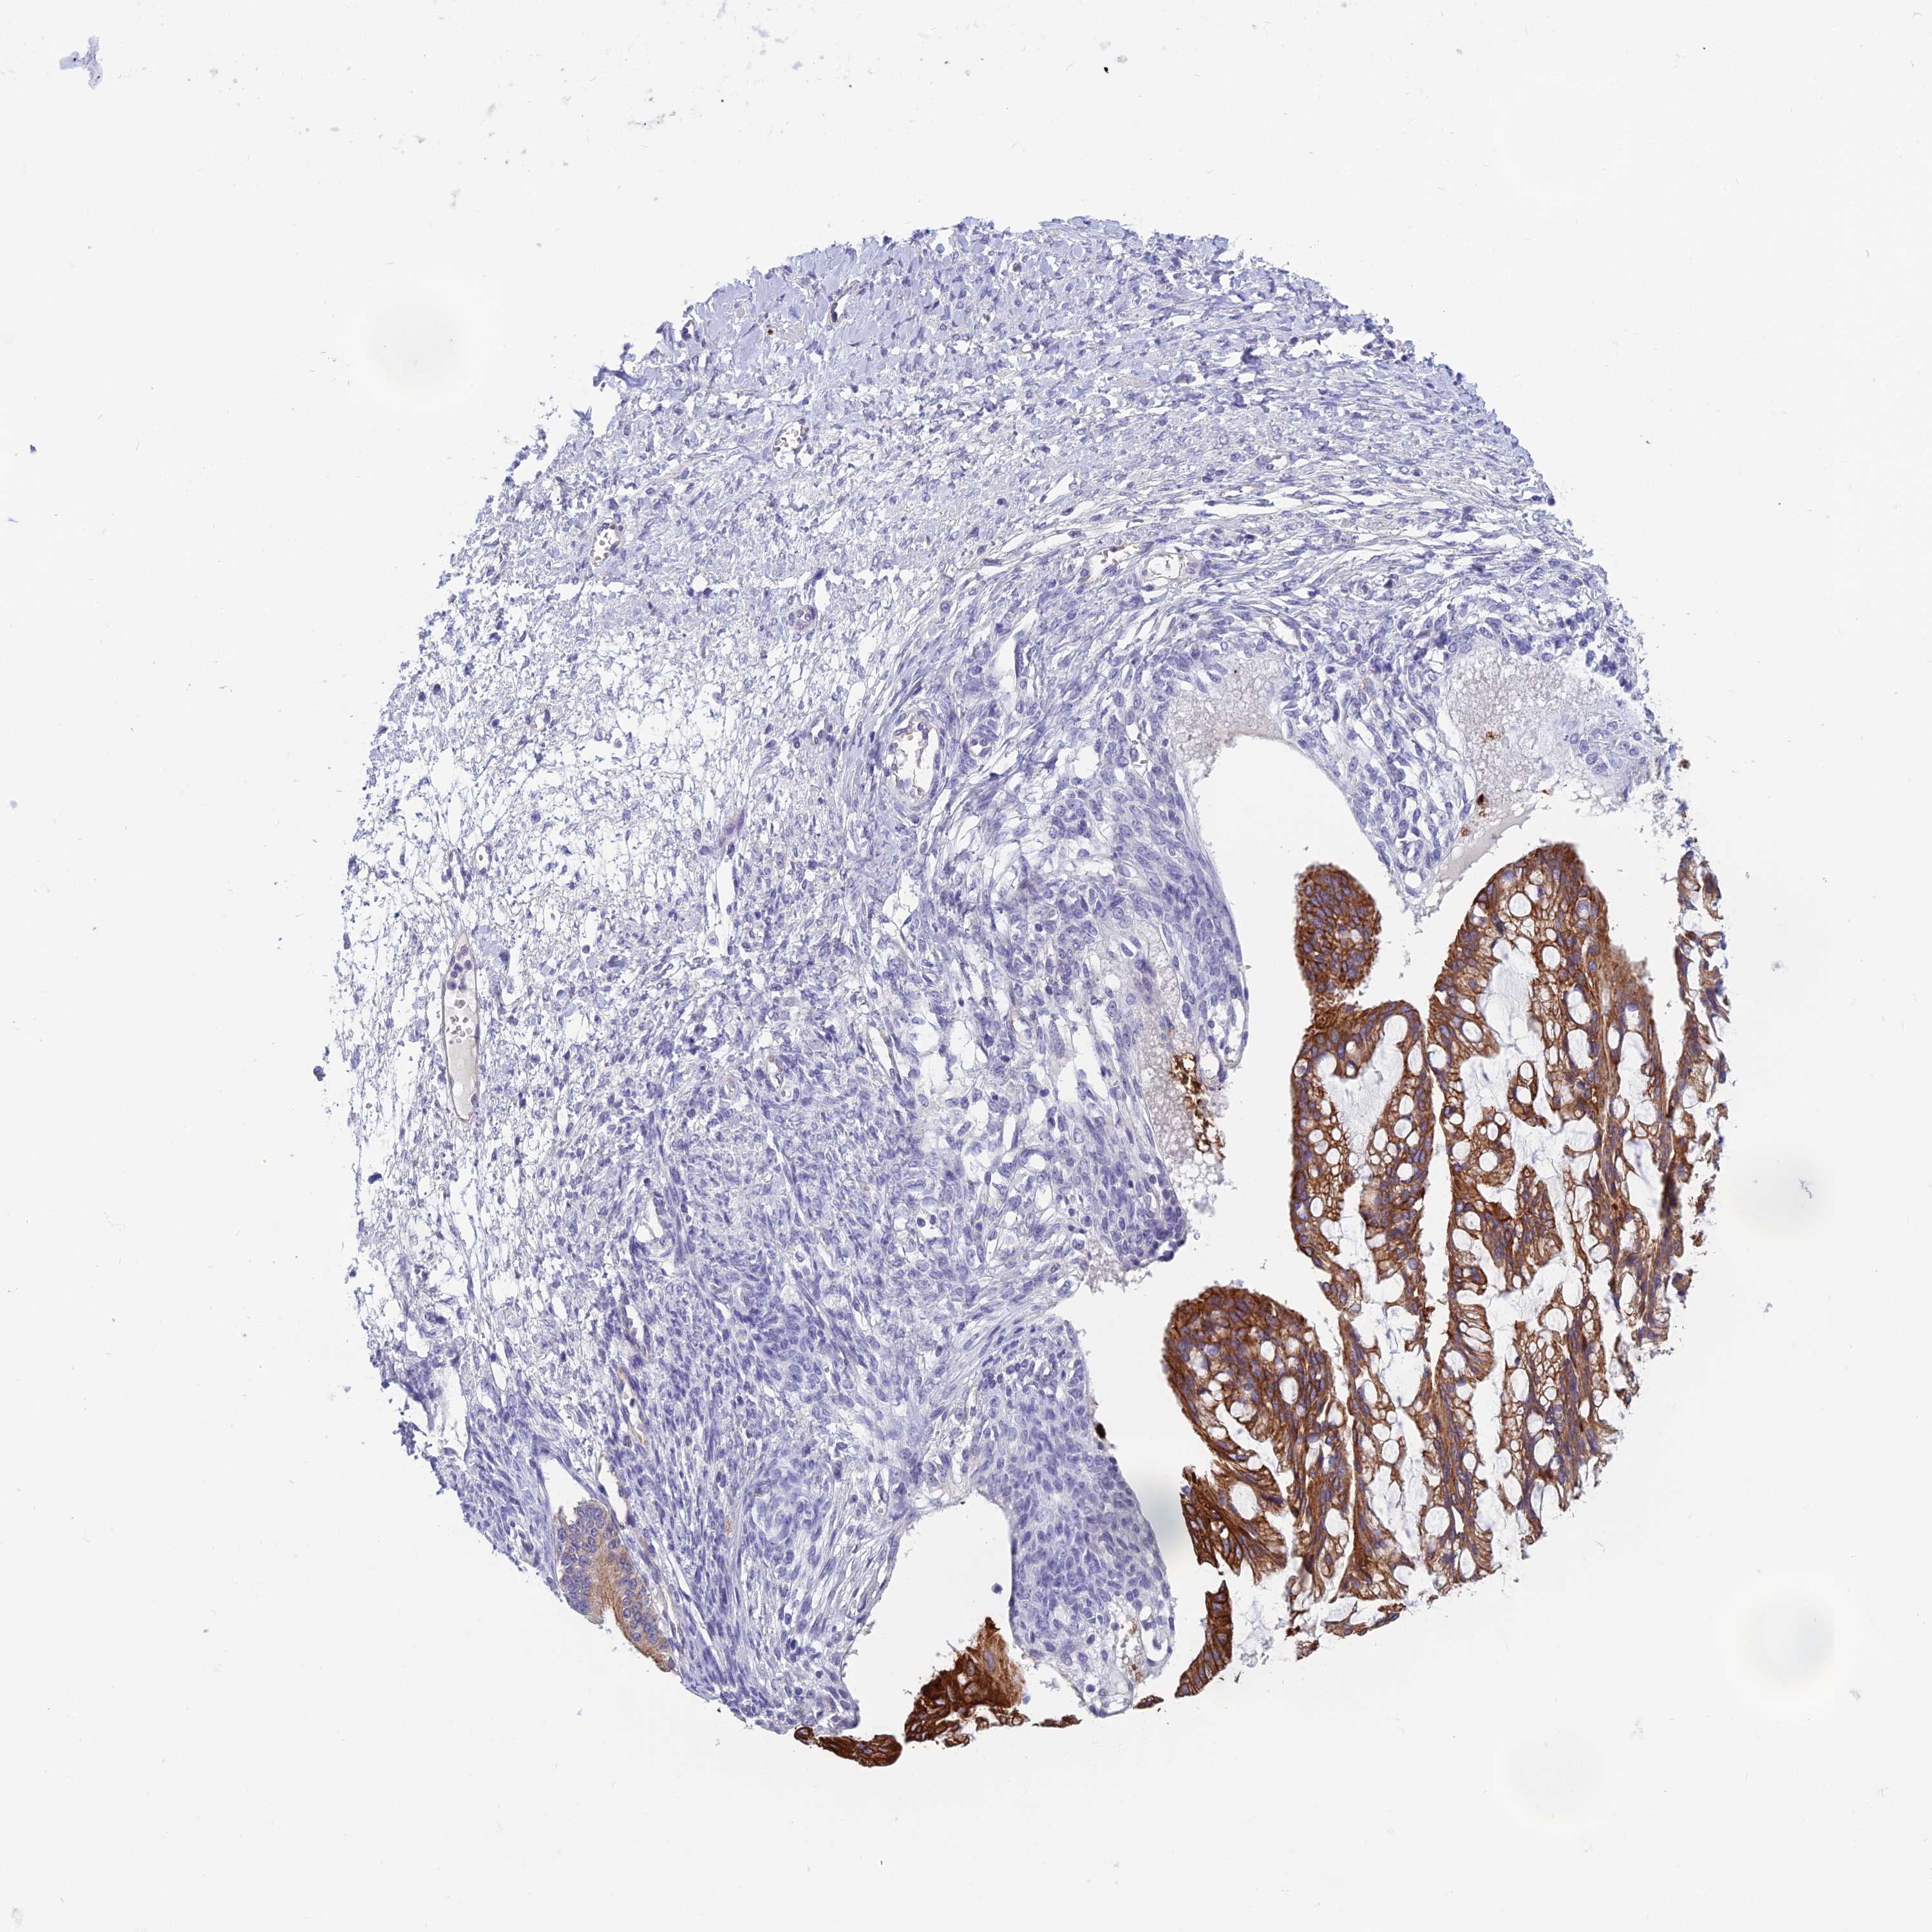

OVARIAN CANCER - Protein expressioni

A mouse-over function shows sample information and annotation data. Click on an image to view it in a full screen mode. Samples can be filtered based on level of antibody staining by selecting one or several of the following categories: high, medium, low and not detected. The assay and annotation is described here.

Note that samples used for immunohistochemistry by the Human Protein Atlas do not correspond to samples in the TCGA dataset.

Antibody stainingi

Antibody staining in the annotated cell types in the current human tissue is reported as not detected, low, medium, or high, based on conventional immunohistochemistry profiling in selected tissues. This score is based on the combination of the staining intensity and fraction of stained cells.

Each image is clickable and will lead to virtual microscopy that enables deeper exploration of all samples and also displays staining intensity scores, fraction scores and subcellular localization as well as patient and tissue information for each sample.

Antibody HPA042881

Staining

Cystadenocarcinoma, serous, NOS

Carcinoma, endometroid

Cystadenocarcinoma, mucinous, NOS

Carcinoma, NOS